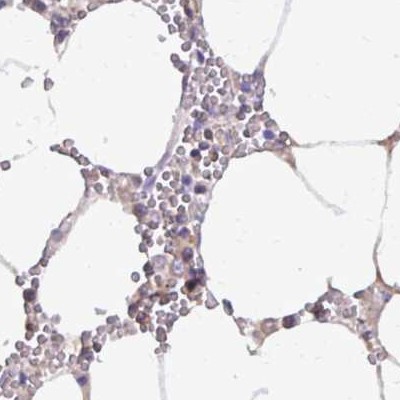

Immunohistochemistry analysis in human liver and pancreas tissues using Anti-CAT antibody. Corresponding CAT RNA-seq data are presented for the same tissues.